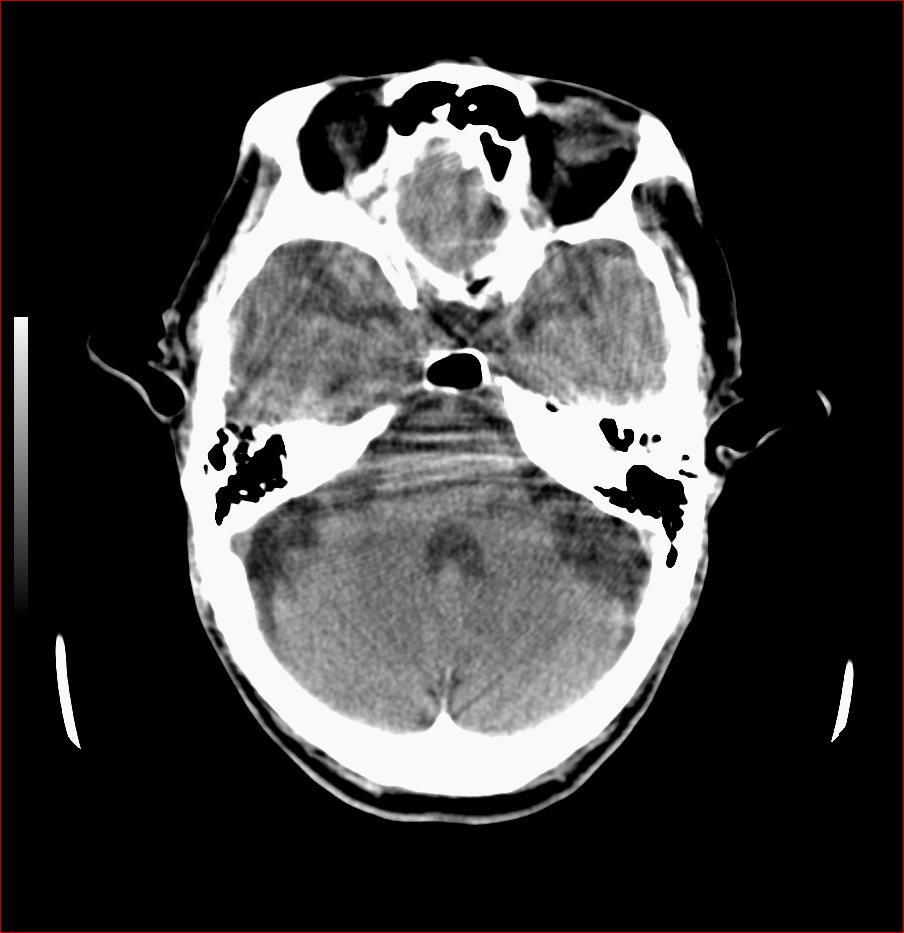

男,84岁,左下肢无力伴口角歪斜1天,血压160/80。请问一下双侧基底节区是脑梗塞吗?

多发脑梗塞,白质疏松,脑萎缩

老年性三联症_多发腔隙性梗死 脑萎缩 脱髓鞘变性.

双侧基底节多发腔隙性脑梗塞;脑白质蔬松;脑萎缩。

1.两侧基底节区及右顶深部脑梗塞。2.右侧外囊区脑软化灶。3.脑萎缩。4.脑白质脱髓鞘改变。